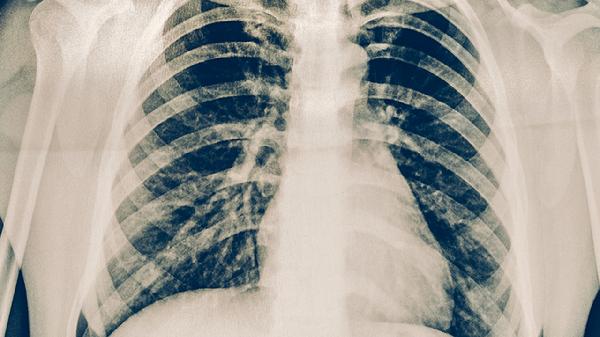

康复期间保持规律作息和良好心态同样重要,可适当补充复合维生素和益生菌。日常饮食注意增加富含锌元素的食物如牡蛎、坚果,有助于促进病灶修复。建议每3个月复查胸部影像学,确保病情持续稳定后再逐步过渡到常规减重模式。